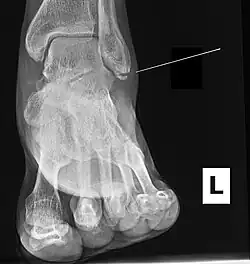

Fracture of the medial malleolus seen on X-ray scan (left ankle)

Common symptoms of a Maisonneuve fracture are pain, swelling, tenderness, and bruising around the ankle joint and inferior (or distal) tibiofibular joint. More specifically, as a pronation-external rotation injury, pain during external rotation of the ankle joint is expected. Additionally, there is a reduced range of motion of the foot and an inability to weight-bear due to ankle pain.[4][7] Pain may also be felt around the medial and lateral aspects of the ankle, and more rarely around the superior (or proximal) tibiofibular joint.[9] Damage to the deltoid ligament or interosseous membrane can cause haemorrhaging around the surrounding tissues, resulting in a localised oedema.[8]